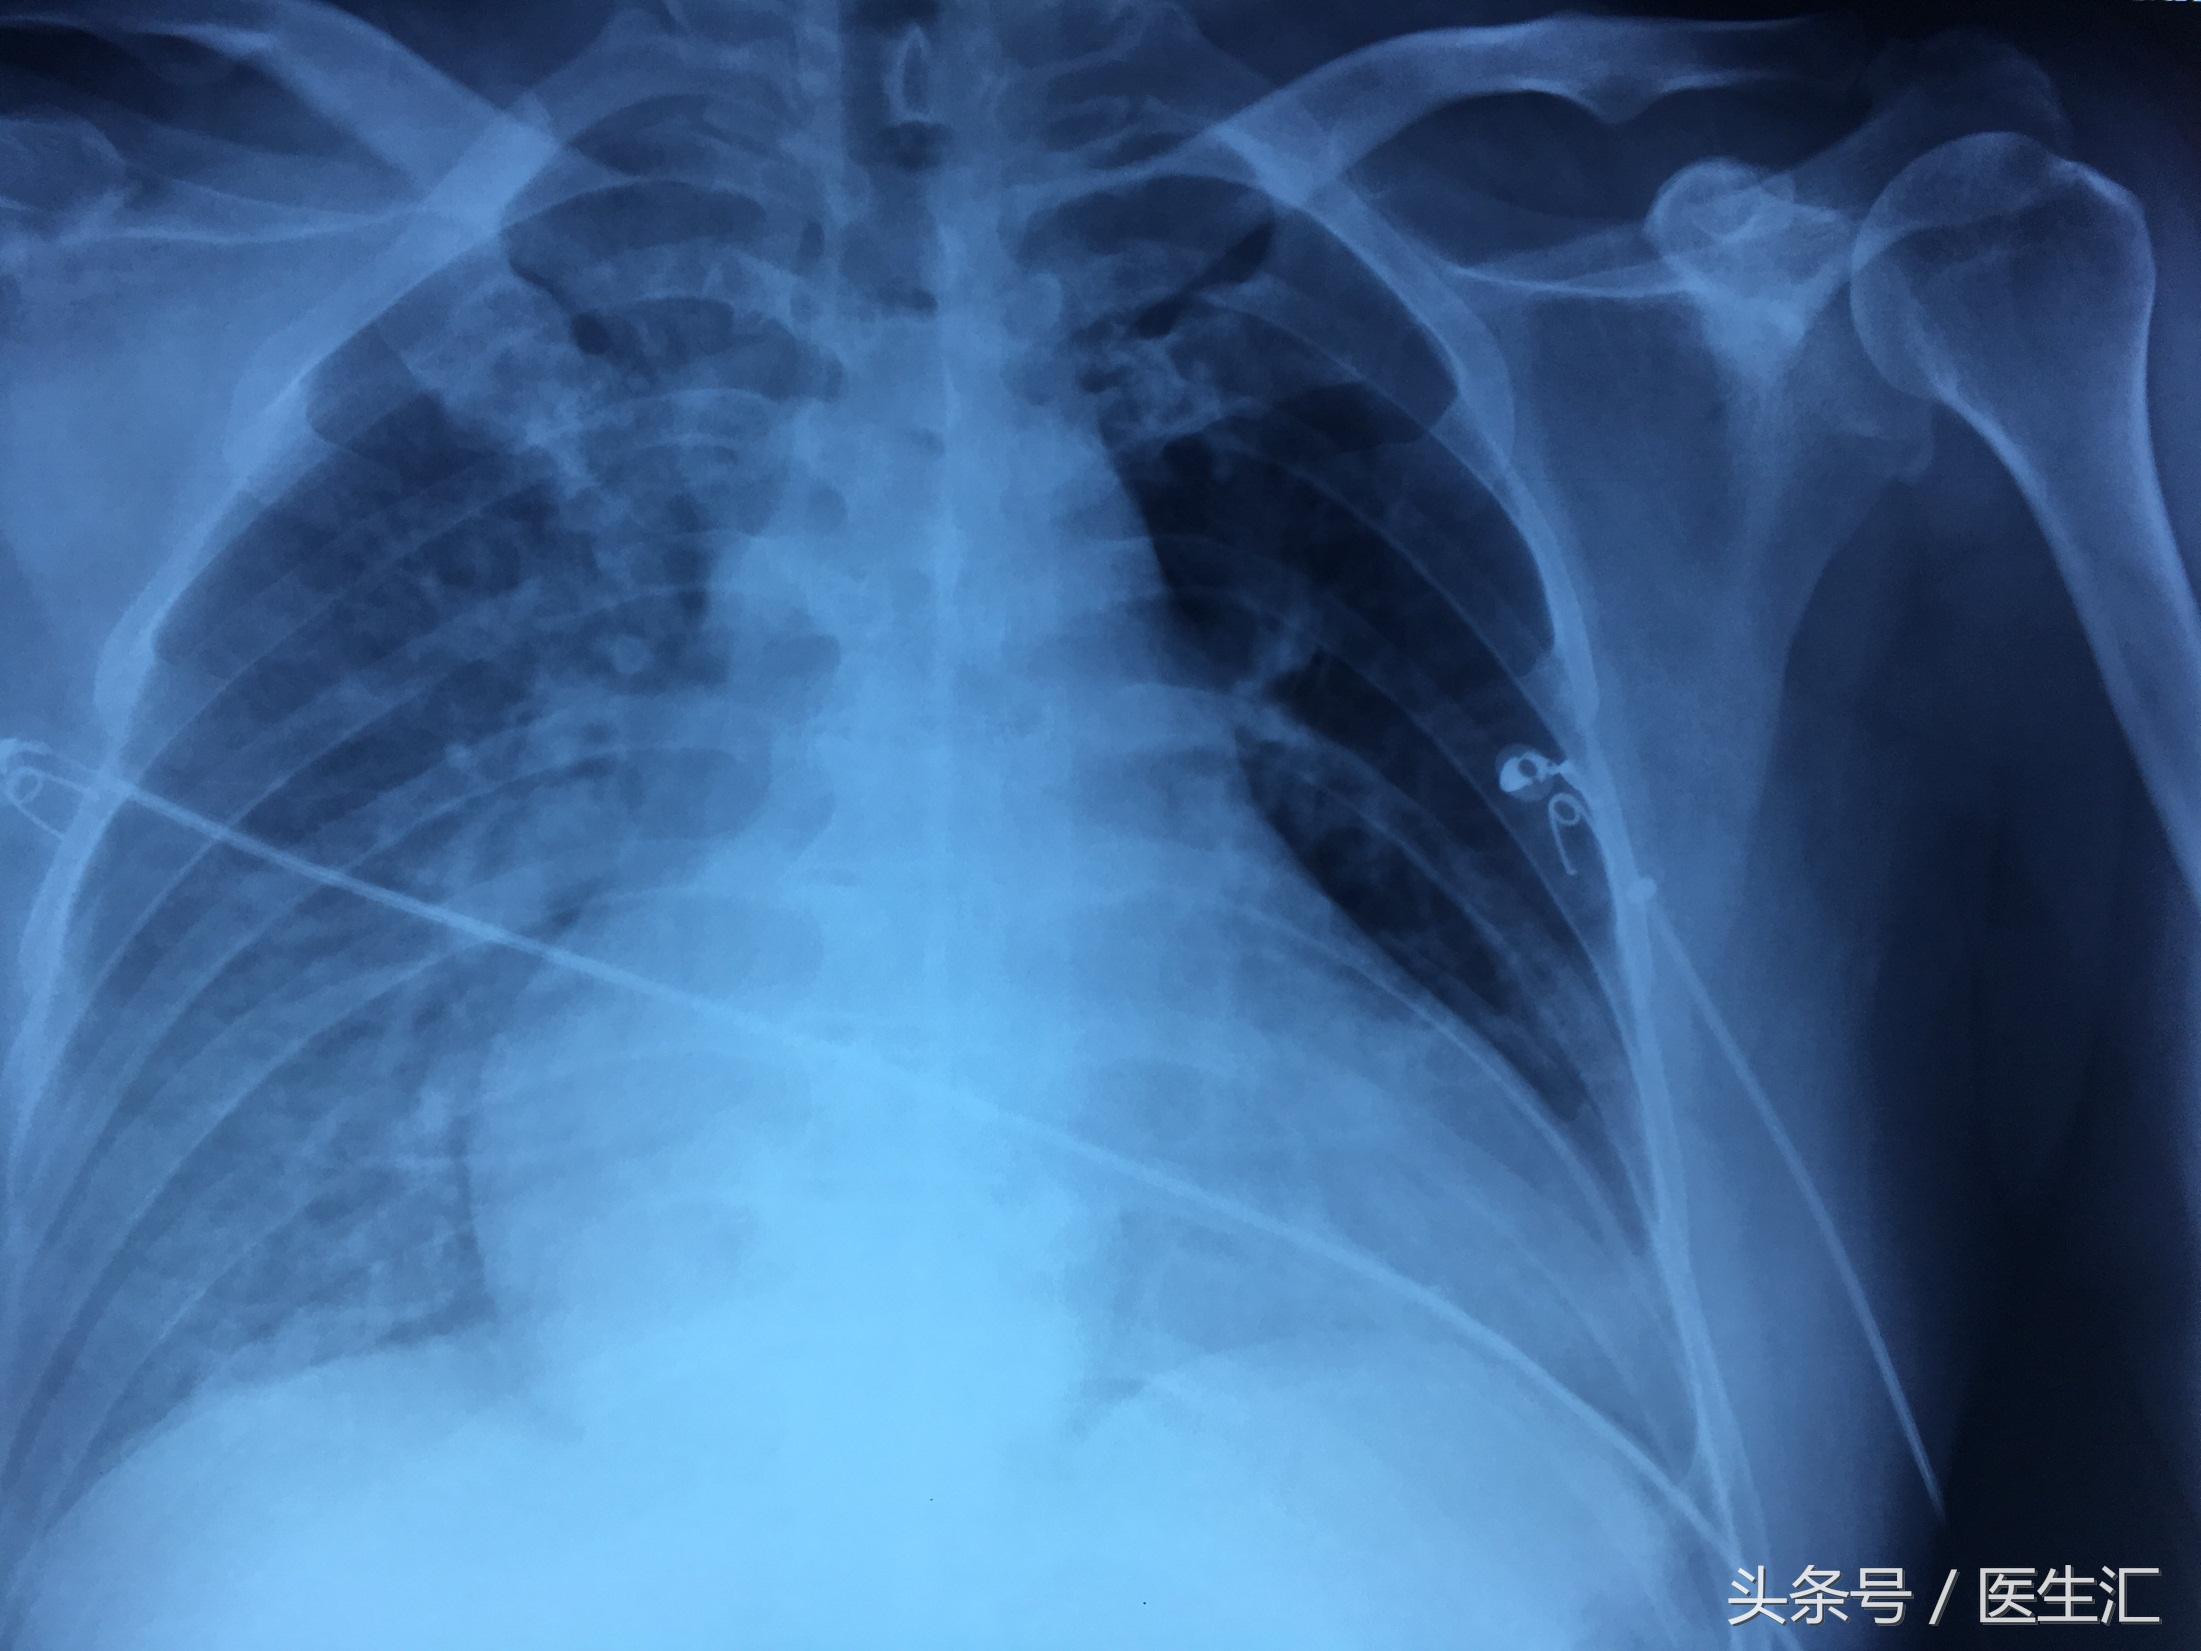

胸片示:

2017-02-24:双肺渗出,心功能不全可能。

2017-02-25:右肺渗出较前吸收,余大致同前。